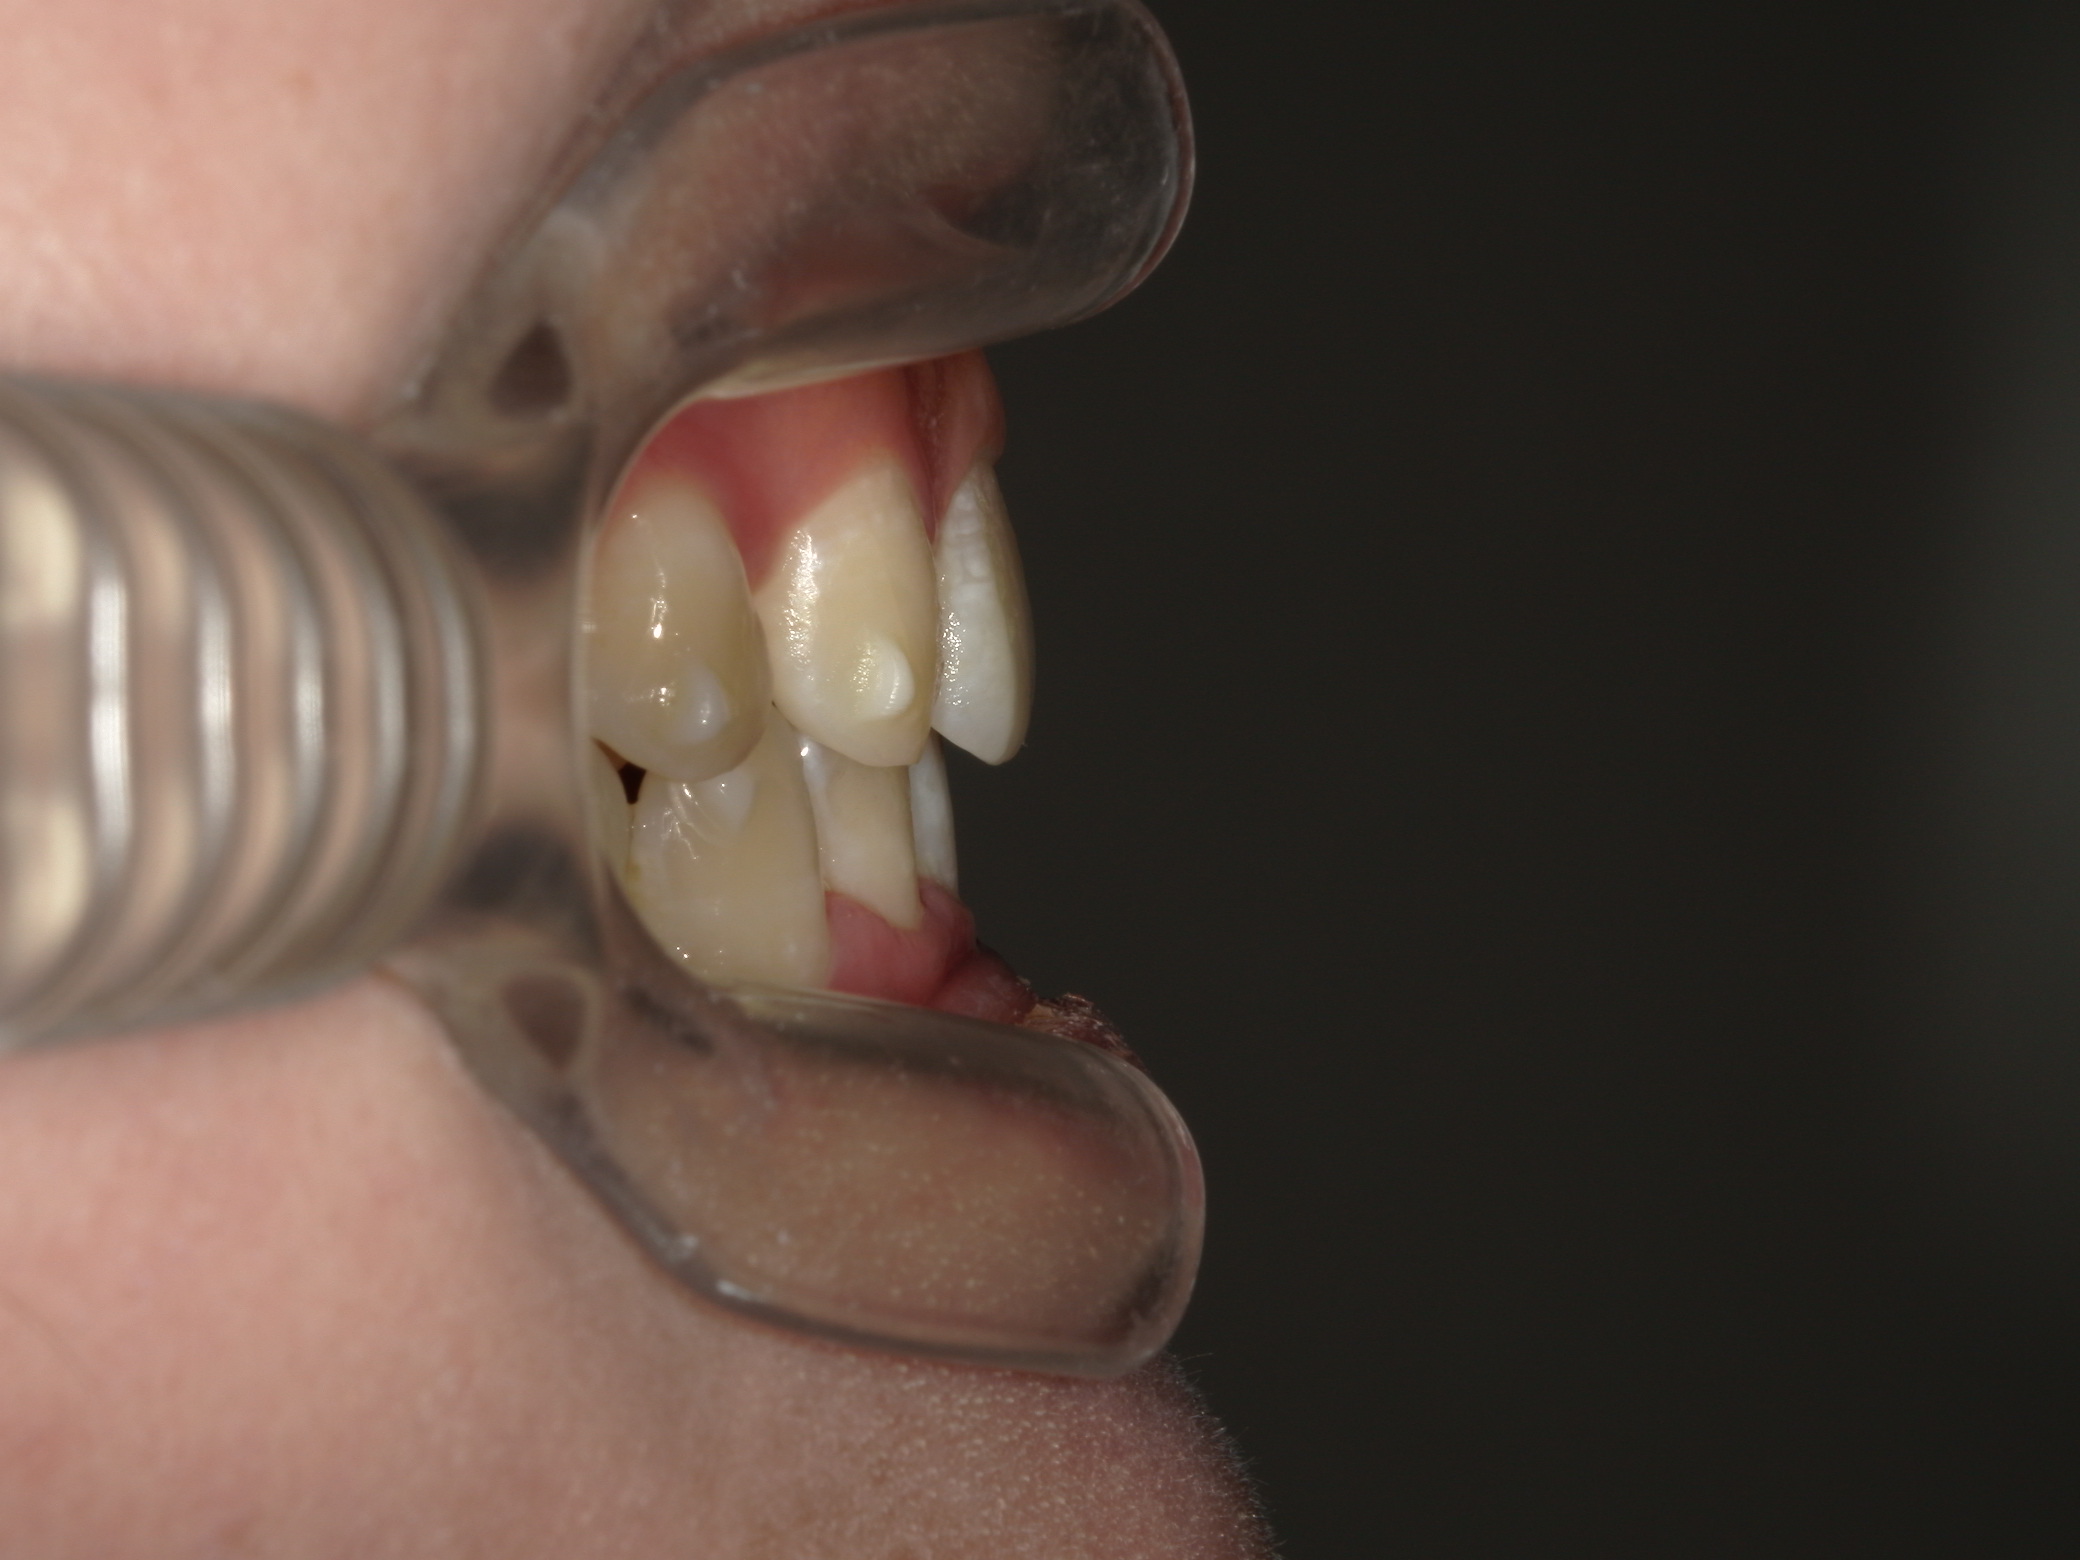

叢生が気になる

| 年齢・性別 | – |

|---|---|

| 主訴 | 叢生が気になる |

| 治療期間・回数 | 1年9ヶ月 |

| 費用 | 1,011,000円 |